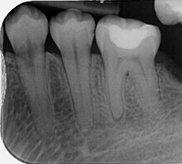

Molar endodontics

Pre-operative